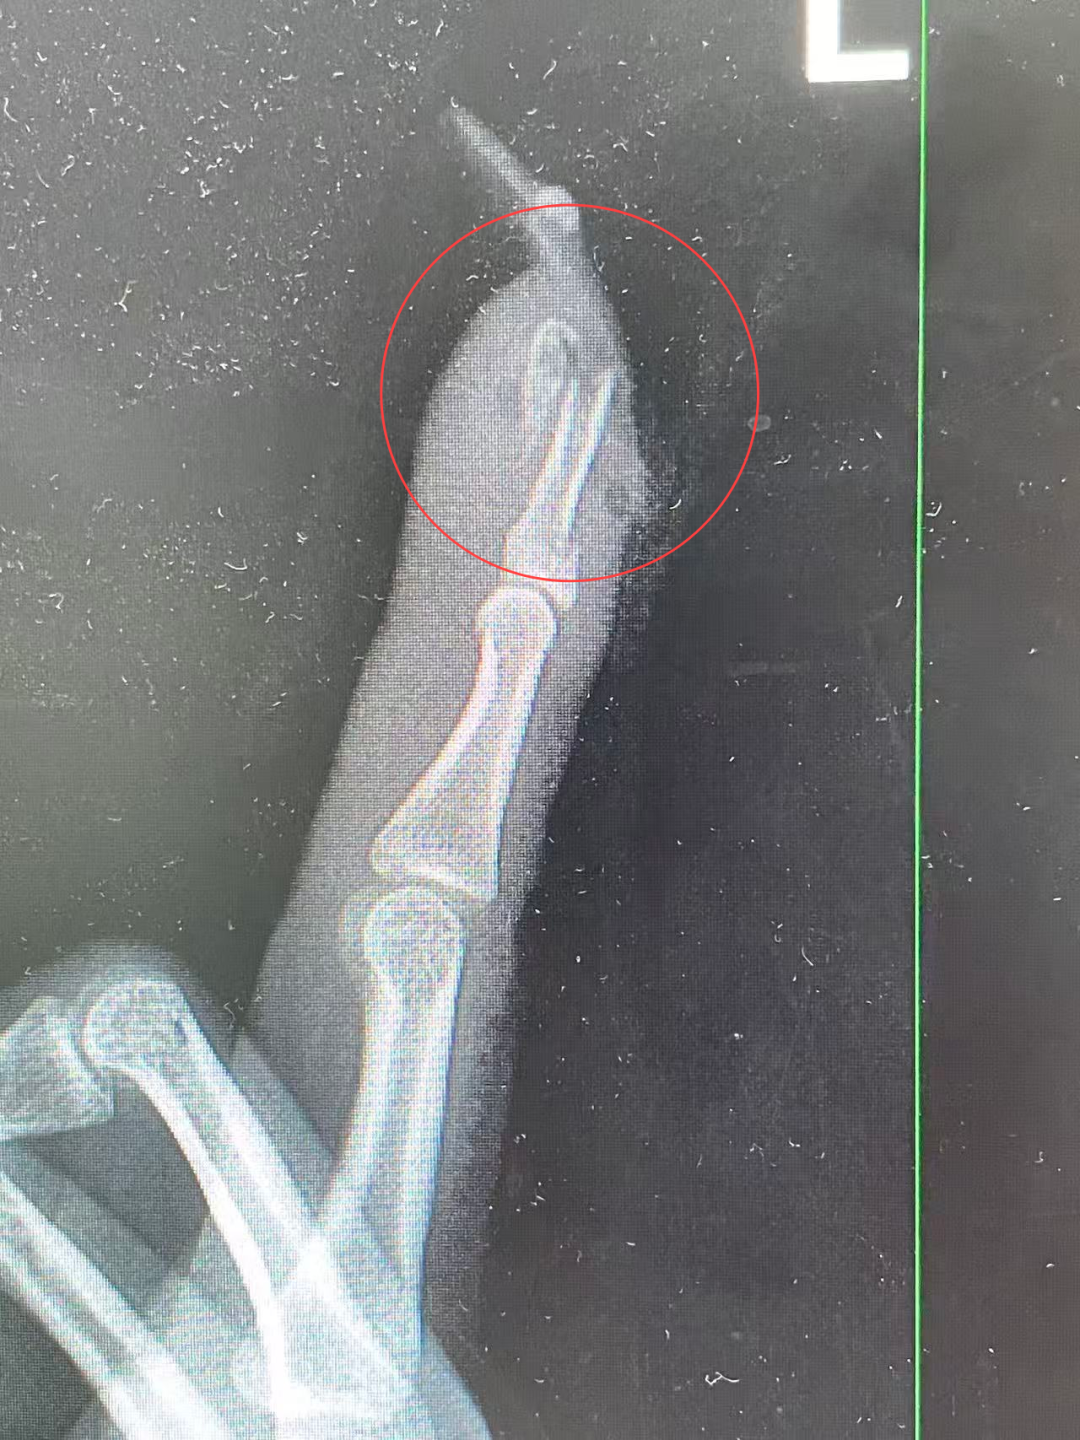

王女士术前的X光影像。

“左手食指指骨骨折,甲床破裂,部分甲床外露,需要手术修复。”接诊的曹立副主任医师检查后作出诊断,并当即对其做了指骨骨折闭合复位内固定术。

术后,王女士情况恢复良好。